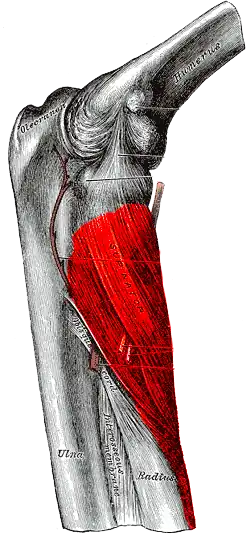

Insertion humérale du muscle supinateur (supinator)

Insertion humérale du muscle supinateur (supinator) Insertions ulnaire et radiale du muscle supinateur (supinator)